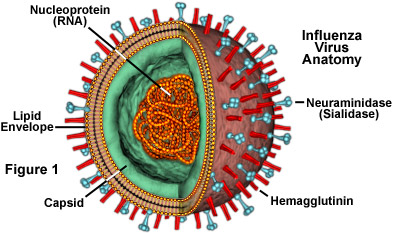

There are many influenza viruses.

There are many influenza viruses.You may have heard of “bird flu” or “swine flu”, specifically H1N1, which had a pandemic outbreak in 2009.

“There are three types of influenza viruses: A, B and C. Human influenza A and B viruses cause seasonal epidemics of disease almost every winter in the United States. The emergence of a new and very different influenza virus to infect people can cause an influenza pandemic. Influenza type C infections cause a mild respiratory illness and are not thought to cause epidemics.

Influenza A viruses are divided into subtypes based on two proteins on the surface of the virus: the hemagglutinin (H) and the neuraminidase (N). There are 17 different hemagglutinin subtypes and 10 different neuraminidase subtypes. Influenza A viruses can be further broken down into different strains. Current subtypes of influenza A viruses found in people are influenza A (H1N1) and influenza A (H3N2) viruses. In the spring of 2009, a new influenza A (H1N1) virus (CDC 2009 H1N1 Flu website) emerged to cause illness in people. This virus was very different from regular human influenza A (H1N1) viruses and the new virus caused the first influenza pandemic in more than 40 years. That virus (often called “2009 H1N1”) has now mostly replaced the H1N1 virus that was previously circulating in humans.” (CDC)

This is why you can get the flu every year. There are many different combinations of the H and N types, such as H1N1, H3N2, etc. Your immune system may have learned to fight H1N2, but not H2N3, etc.

H1N1 cause the Spanish Flu. H3N2 caused the Hong Kong Flu in 1968. H2N2 caused the Asian Flu in 1957.